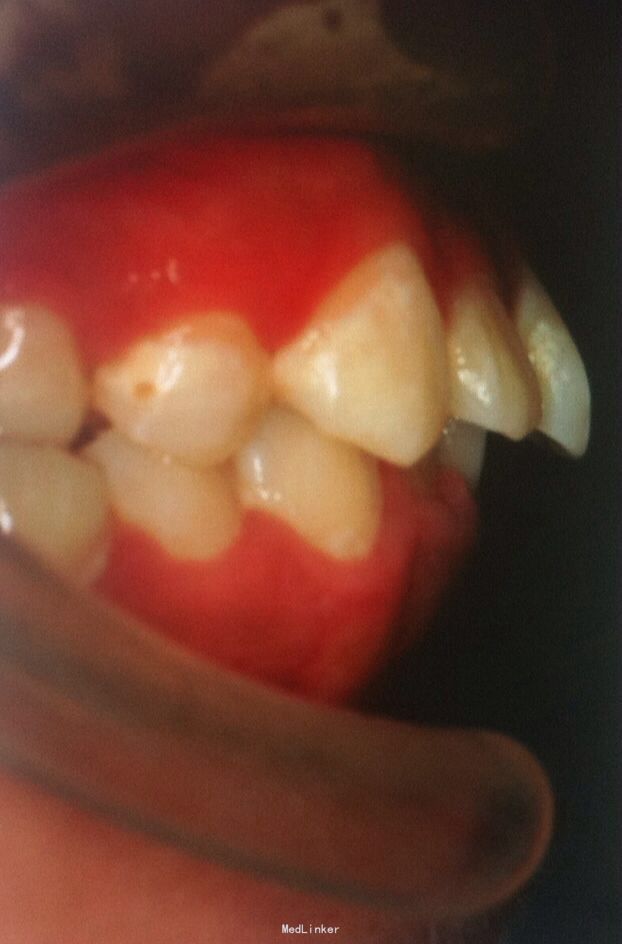

恒牙期 左侧磨牙中性关系,右侧远中关系 前牙三度深覆合 上合牙列中度拥挤,下颌重度拥挤 下颌中线偏右 关节有弹响